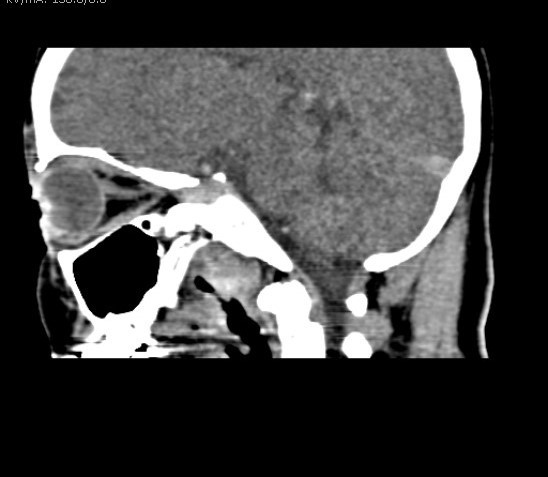

Exames de tomografia são muito confiáveis e seguros, realizados por aparelho de raios X de alta resolução que gira em torno do corpo, fazendo radiografias transversais. É capaz de obter imagens em fatias do corpo, gerando imagens tridimensionais. O exame é indolor, o paciente deve permanecer imóvel e é de rápida duração.